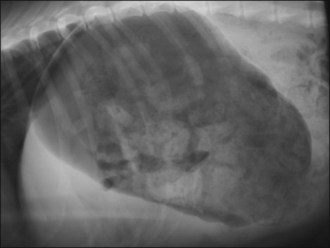

Abdominal radiography reveals convoluted loops of tubular fluid opacity in the caudal abdomen with dorsal displacement of the descending colon (Figure 29.9), and ultrasonography shows enlarged uterine horns distended with hypoechoic fluid (Figure 29.10).

Figure 29.9 Right lateral abdominal radiograph in a dog with pyometra. Convoluted loops of tubular fluid opacity are visible in the caudal abdomen.